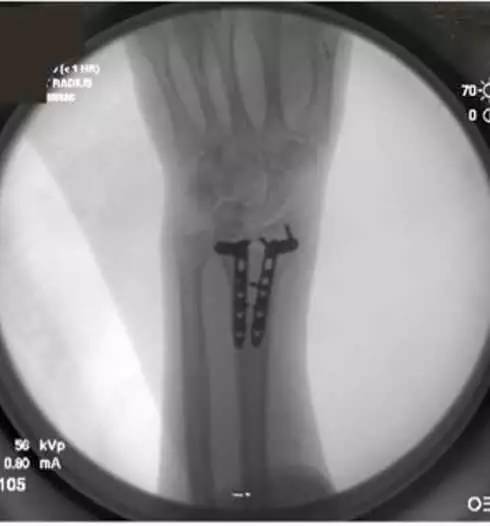

6. 内固定完成后,拆除克氏针,缝合切口,骨折得到复位(图 4)。

图 4 骨折复位良好